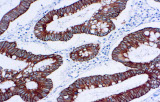

A imunohistoquímica (IHQ) com anticorpos primários CE/IVD é essencial para o diagnóstico e classificação precisos de malignidades ginecológicas e mamárias. Estes anticorpos permitem a deteção precisa de marcadores tumorais e proteínas celulares, apoiando o diagnóstico diferencial e guiando estratégias terapêuticas personalizadas.

Estudos recentes destacam o valor diagnóstico das proteínas do complexo SWI/SNF, particularmente ARID1B, na identificação de malignidades ginecológicas desdiferenciadas e indiferenciadas – tumores agressivos com mau prognóstico. A IHQ de ARID1B oferece elevada especificidade e está cada vez mais integrada em painéis diagnósticos para melhorar a precisão. Painéis com marcadores adicionais também apoiam a diferenciação de sarcomas uterinos, aumentando a exatidão diagnóstica. Evidência emergente sugere que ARID1B pode representar um alvo terapêutico potencial no carcinoma ovárico de células claras, embora as aplicações clínicas permaneçam em fase investigacional.

Anticorpos primários contra recetor de estrogénio (ER), recetor de progesterona (PR), HER2 e Ki-67 continuam a ser a pedra angular da classificação e decisões terapêuticas no cancro da mama. Estes anticorpos estão validados clinicamente e marcados CE/IVD para garantir deteção fiável e reproduzível de biomarcadores – crucial para orientar terapia hormonal e estratégias de tratamento direcionado.